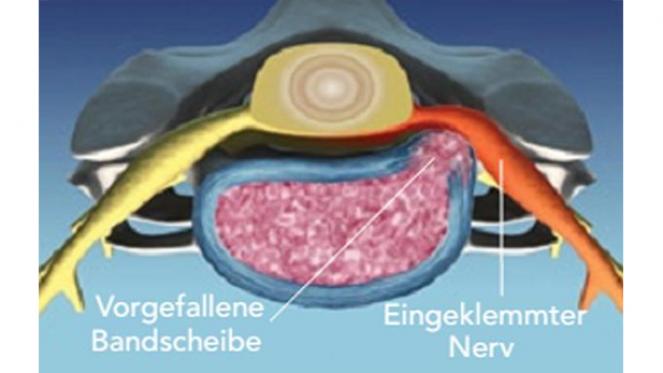

Mit zunehmendem Lebensalter kann es zu verschleißbedingten Rissen am äußeren Ring der Bandscheibe (Faserring) und zu einem Austritt des gallertartigen Kerns kommen. Dieser kann die benachbarten Nervenwurzeln oder das Rückenmark zusammendrücken und zu lokalen oder ausstrahlenden Schmerzen in den Armen und Beinen, ggf. auch mit Sensibilitätsstörungen und motorischen Ausfällen, führen.